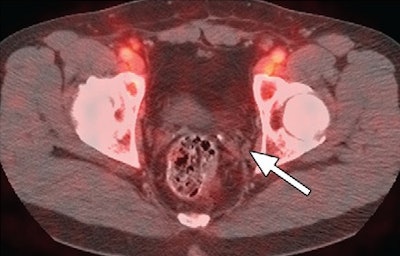

Images of a patient who underwent a radical prostatectomy. Fused PET/CT scan with FACBC (above) shows 5-mm recurrence in the left obturator lymph node. There is no uptake of indium-111 with SPECT/CT (below) in same region (arrow). Images courtesy of Radiology.